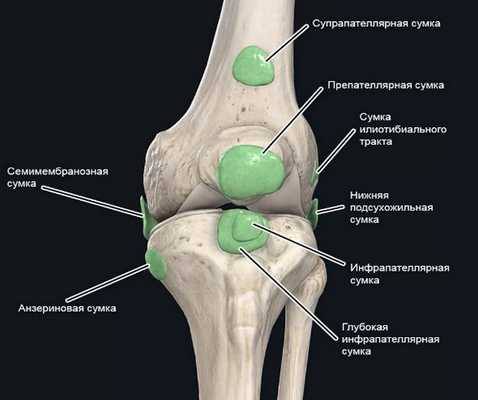

Коленный сустав — один из наиболее сложных суставов в теле человека. Он имеет в своём составе большое количество синовиальных сумок:

- наднадколенниковая (супрапателлярная);

- преднадколенниковая (препателлярная);

- поднадколенниковые поверхностная и глубокая (инфрапателярные);

- сумка гусиной лапки (анзериновая);

- сумка медиальной (внутренней) боковой связки;

- сумка латеральной (наружной) боковой связки;

- сумка илиотибиального тракта;

- сумка сухожилия полуперепончатой мышцы (полуперепончатая);

- сумка медиальной (внутренней) головки икроножной мышцы — икроножная сумка;

- сумка подколенной мышцы — подколенная.

Бурсит может возникнуть в любой из этих видов сумок [10] .

Синовиальные сумки коленного сочленения